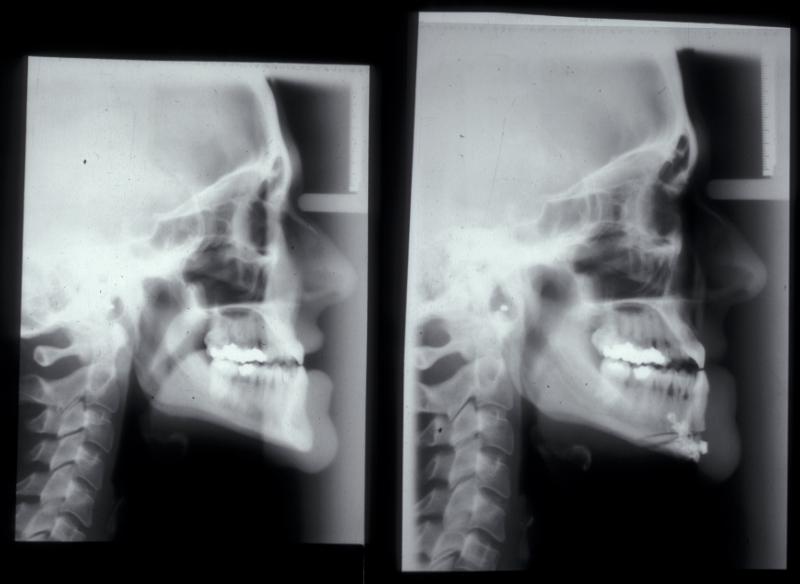

Genioplasty procedures use very similar principles to those of orthognathic procedures (Figure 10).

The chin is approached from an intraoral incision that exposes and protects the mental nerves. Bone cuts are made horizontally to retain the lingual muscle attachments. The chin is reduced by excising a middle portion of bone and inset to preserve the aesthetics of the cortical chin shape. It can be advanced by sliding forward. It is internally fixed using miniplates (Figure 11). Small asymmetries can be corrected in this way.

Augmentation genioplasty uses implants, either made from synthetic materials or a bone graft taken from the hip. The implant can be inserted by a skin incision under the chin (which is invisible from a front view) which is preferable for inert non-biological implants which have a lower inherent resistance to infection. Iliac crest grafts or sliding advancement genioplasties are far more common and a number of specific intra-oral miniplates have been devised to aid this surgery which also has a role in managing obstructive sleep apneoa. Almost inevitably, the aesthetic results using somebody’s own bone are superior to those achieved by using synthetic materials.

Genioplasty approaches, are used to correct other facial contours as well. If facial contours appear excessive because of underlying bone, this can in part be corrected by osteotomies (Figure 12).